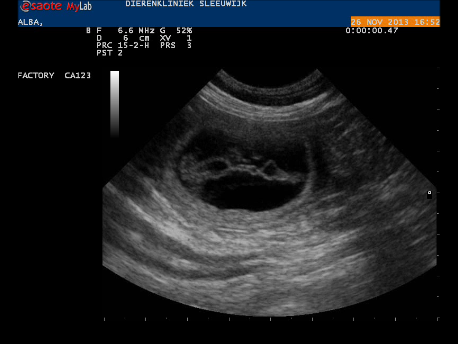

Voor zover we het niet al zeker wisten, is het nu wel zeker: Alba is drachtig!

Gisteren hebben we een echo laten maken bij Dierenkliniek Sleeuwijk. Zodra de echokop haar buik raakte, sprongen er een aantal vruchtblaasjes in beeld. Het blijft prachtig om te zien! De dierenarts heeft niet precies geteld, dat hoeft voor ons ook niet, maar het is duidelijk dat het geen klein nest zal worden. De vruchtjes zagen er goed ontwikkeld uit, en hoewel er ook in dit stadium nog van alles kan gebeuren gaan we er vanuit dat Alba over 4,5 week prachtige pupjes gaat krijgen.

Momentopname 1 (27-11-2013 15-09)